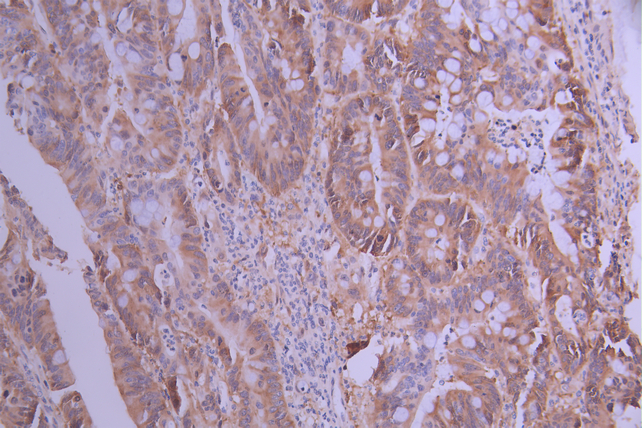

IHC image of CSB-RA786202A0HU diluted at 1:100 and staining in paraffin-embedded human colorectal cancer performed on a Leica BondTM system. After dewaxing and hydration, antigen retrieval was mediated by high pressure in a citrate buffer (pH 6.0). Section was blocked with 10% normal goat serum 30min at RT. Then primary antibody (1% BSA) was incubated at 4°C overnight. The primary is detected by a Goat anti-rabbit polymer IgG labeled by HRP and visualized using 0.05% DAB.